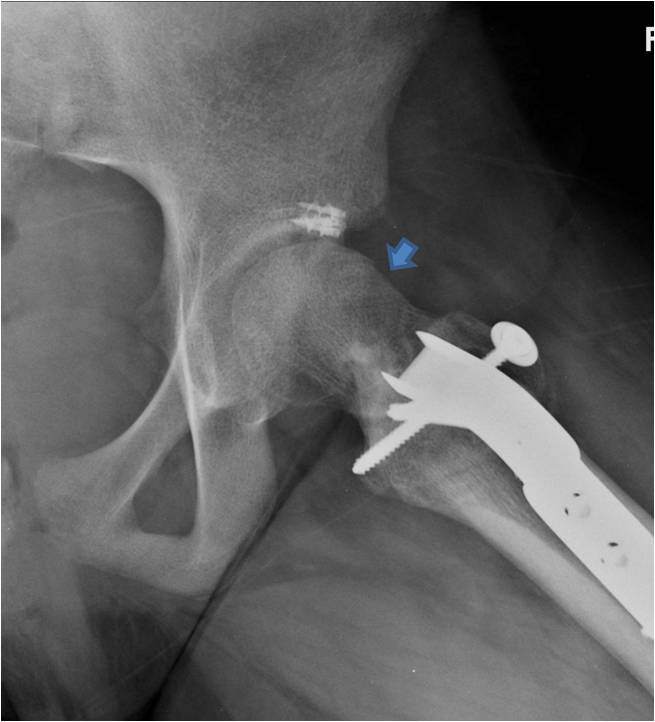

From old.johnclohisymd.com

PAO and surgical dislocation for a “Perthes” deformity in a 29 year old Hip Pain After Pao Surgery Periacetabular osteotomy (pao) is a surgical treatment for younger patients (40 and under) who have hip dysplasia resulting from a deformity in. For young people with hip dysplasia and other hip conditions, pao can reduce pain, improve hip function and quality of life, and allow them to live physically active lives, including playing sports. Pao surgery treats hip dysplasia, leading. Hip Pain After Pao Surgery.